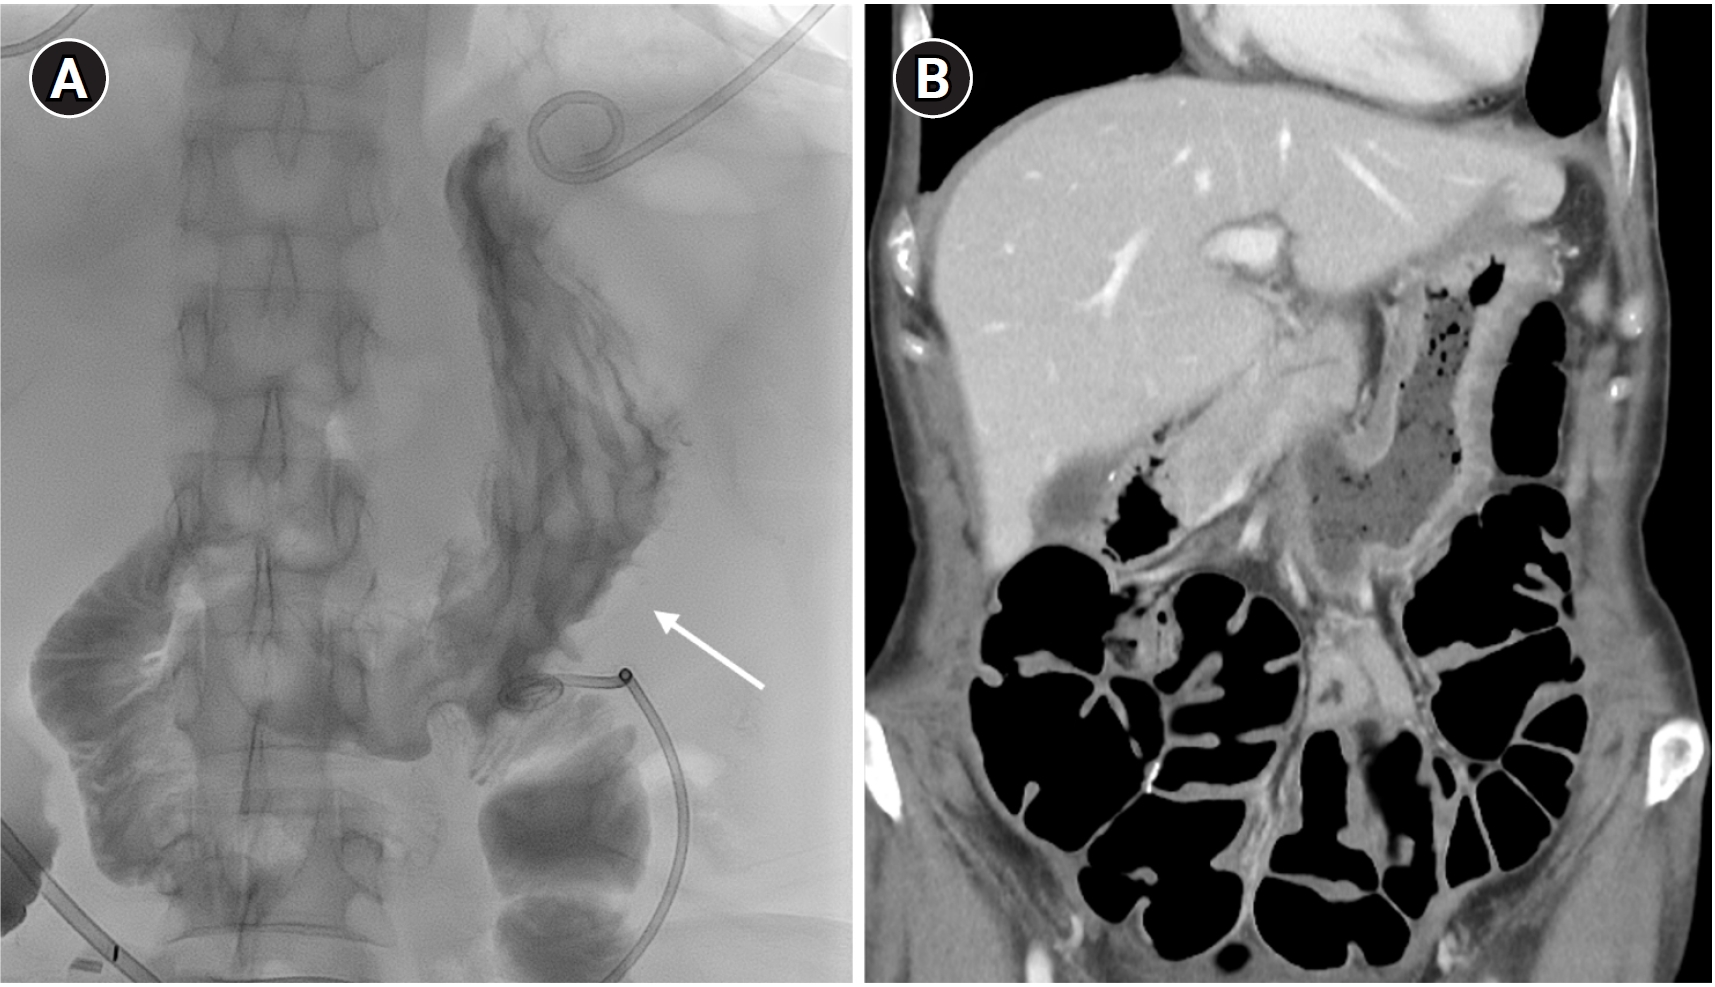

Post-closure gastrography with water-soluble contrast medium demonstrated no leakage at the puncture site (

Fig. 3A). To ensure the safety of closure site and to manage ongoing jejunal leakage, the patient was kept fasting for 6 days before starting a soft diet. The patient subsequently underwent an additional small bowel resection for refractory bowel leakage. Clinical follow-up and CT after 10 months showed no procedure-related adverse events (

Fig. 3B).

Fig. 3.Follow-up. (A) Immediate post-procedural gastrography with oral contrast medium shows no leakage at the puncture site (arrow) and no structural deformity. (B) Ten-month follow-up CT shows no leakage or deformity of the stomach.